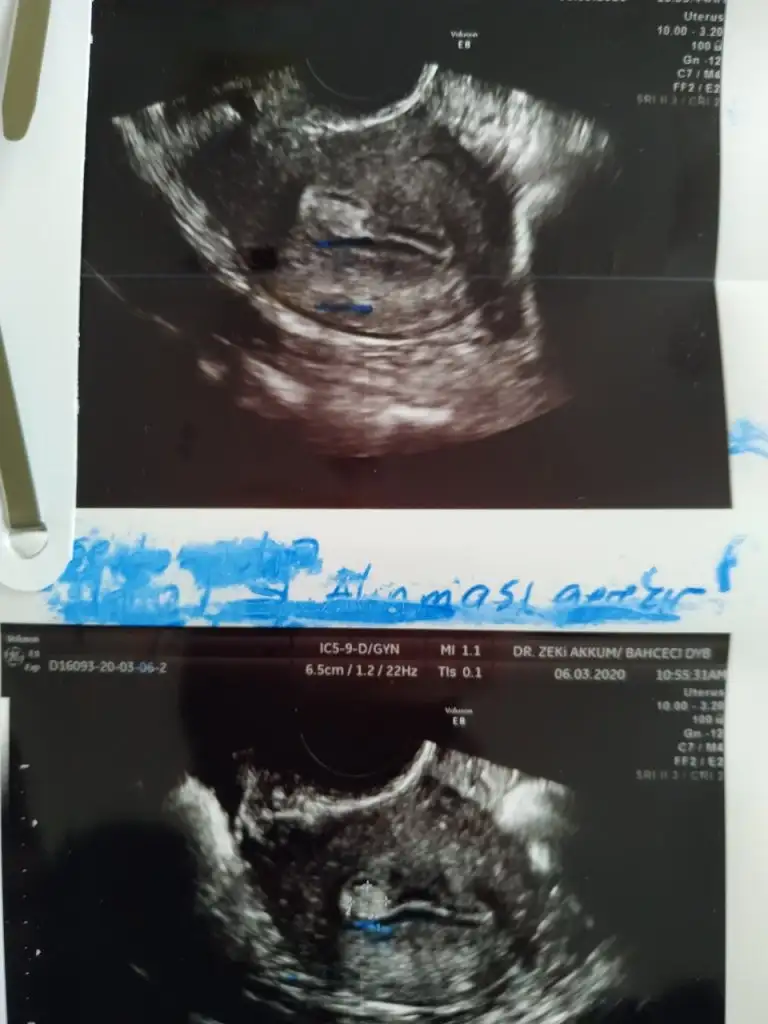

kızlar moralim bozuk :( tüp bebek tedavimde ilaçları kullanmaya başladım yumurta boyutunu kontrol amaçlı gittiğimizde doktorum rahmin içinde polip benzeri bi şey gördü görüntünün yanıltıcı olabileceğini ve emin olmak için yumurta toplama işleminde histereskopi yapacağını söyledi benimle aynı durumu yaşayan kızlar var mı bilgilerini paylaşırsa sevinirim

• polip.webp

polip.webp

kızlar moralim bozuk :KK43: tüp bebek tedavimde ilaçları kullanmaya başladım yumurta boyutunu kontrol amaçlı gittiğimizde doktorum rahmin içinde polip benzeri bi şey gördü görüntünün yanıltıcı olabileceğini ve emin olmak için yumurta toplama işleminde histereskopi yapacağını söyledi benimle aynı durumu yaşayan kızlar var mı bilgilerini paylaşırsa sevinirim

tüp bebek denemesinde önce mi yaptırsaydım diyorum ya da ilaçlarda polip yapmış da olabilir çünkü ben 3 senedir ara ara kontrole giderim daha önce böyle bi durum yoktu malum ağır hormon ilaçları kullanıyoruz :(

tüp bebek denemesinde önce mi yaptırsaydım diyorum ya da ilaçlarda polip yapmış da olabilir çünkü ben 3 senedir ara ara kontrole giderim daha önce böyle bi durum yoktu malum ağır hormon ilaçları kullanıyoruz :KK43: